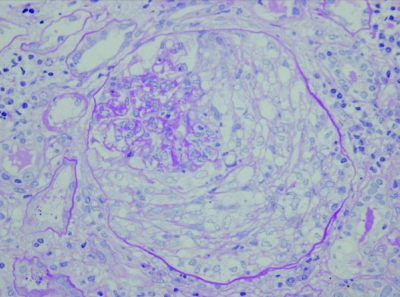

尿所見:蛋白3+、糖(-)、潜血2+、沈渣は赤血球 30〜49/HPF、顆粒円柱 1〜4/HPF。血液所見:赤血球 311 万、Hb 9.5 g/dL、Ht 29 %、白血球 9,500(分葉核好中球 63 %、好酸球 4 %、好塩基球 1 %、単球 7 %、リンパ球 25 %)、血小板 24万。血液生化学所見:総蛋白 6.8 g/dL、アルブミン 3.0 g/dL、尿素窒素 69mg/dL、クレアチニン 4.3 mg/dL、血糖 122 mg/dL、HbA1c 6.3 % (基準4.6〜6.2)、総コレステロール 266 mg/dL、トリグリセリド 160 mg/dL、Na 140mEq/L、K 6.0 mEq/L、Cl 110 mEq/L、Ca 8.6 mg/dL、P 5.0 mg/dL。免疫血清学所見:CRP 3.5 mg/dL、CH50 54 U/mL(基準 30〜40)。腎生検の PAS 染色標本を別に示す。

最も考えられるのはどれか。

a. 糖尿病腎症

b. 悪性腎硬化症

c. 顕微鏡的多発血管炎

d. 感染後急性糸球体腎炎

e. コレステロール塞栓症